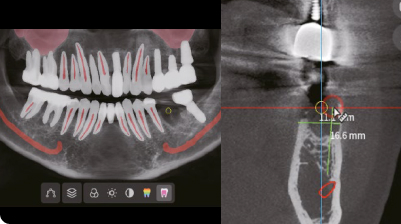

Точное и простое измерение

Всего два шага — выбор зуба и измерение — позволяют клиницистам создавать точные поперечные срезы для более быстрого и точного планирования имплантации.

Простая установка имплантатов

Всего несколько лёгких шагов для установки имплантатов без лишнего стресса.